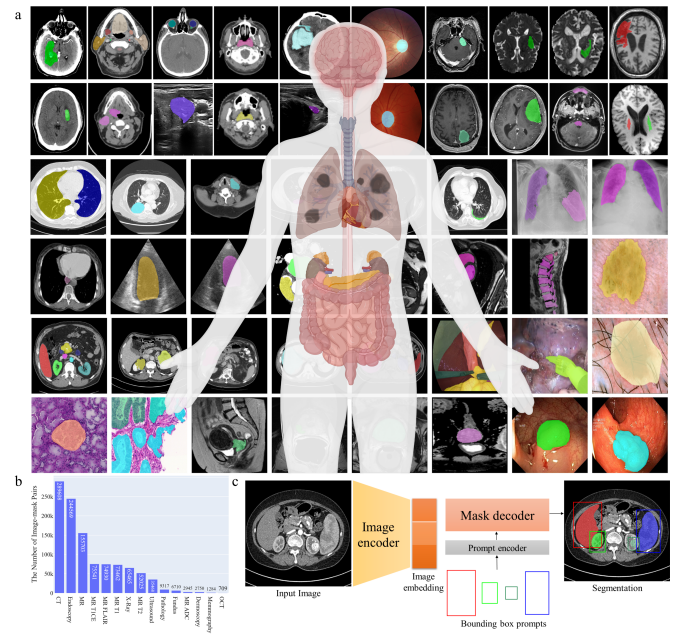

SAM for Medical Segmentation

Medical SAM 总览

MedSAM:通过在大规模医学分割数据集上微调 SAM,创建了一个用于通用医学图像分割的扩展方法 MedSAM。这一方法在 21 个 3D 分割任务和 9 个 2D 分割任务上优于 SAM。

MedSAM

总体来说,通过各种微调、适配和修改方法,SAM 已被成功适应了用于医学图像分割的任务,涵盖了从器官、病变到组织的不同医学图像。这些方法也突出了将自然图像的深度学习技术迁移到医学领域的潜力和挑战。在未来,SAM 及其变体可能会继续推动医学图像分析领域的进展。